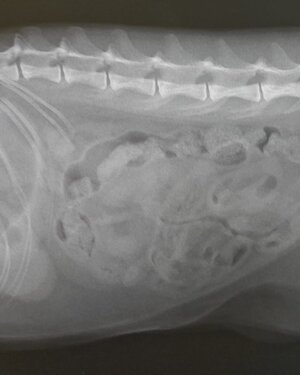

Radiologia

La radiologia è la tecnica di diagnostica per immagini di più largo impiego in medicina veterinaria.

Presso la nostra struttura si effettuano indagini diagnostiche di questo tipo sia per la valutazione di ampi distretti anatomici (torace e addome nel loro insieme), che in ambito ortopedico, nei soggetti in accrescimento, nei pazienti adulti e negli anziani.